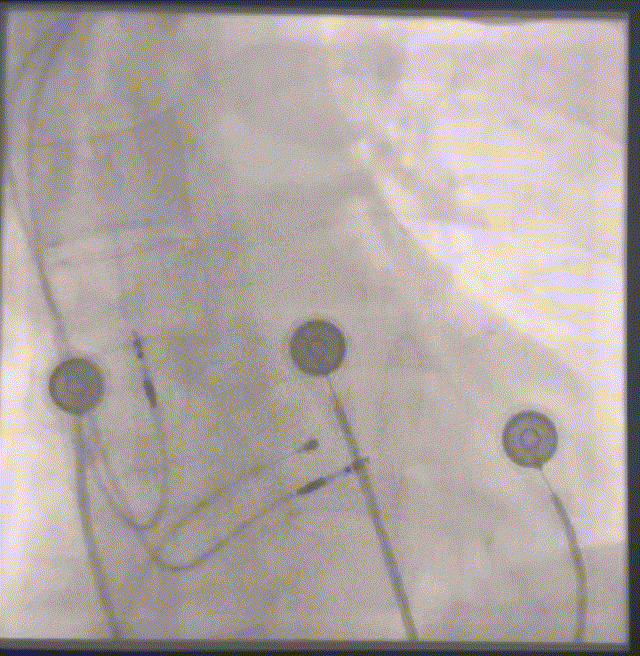

图6 左前斜判断植入位点

图7 使用鞘管的造影功能判断植入位点